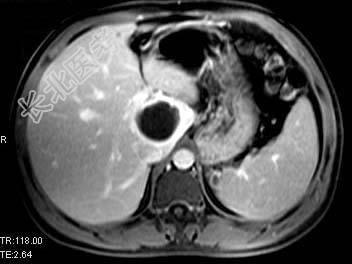

单项选择题根据所提供的图像,最可能的诊断是 ( )

A、肝囊肿

B、胆管细胞癌

C、先天性胆管扩张

D、肝脓肿

E、以上都不是